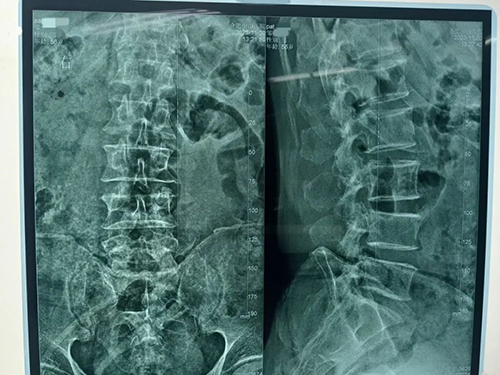

术前

我院骨科团队第一时间了解患者情况,为其安排各项检查。邹先生被确诊为:L4、5椎间盘突出症(游离型),马尾神经综合征。患者大小便功能障碍已经5天,且症状逐渐加重,情况较为紧急,于是骨科团队为邹先生在急诊全麻下行:L4/5椎间盘脱出症腰后入路+L4、L5椎体钉棒内固定+全椎板切除术+椎管扩大减压神经根松解+椎间植骨融合器融合术,手术顺利,术中成功固定L4、L5椎体钉棒,并摘除卡压神经根处的髓核组织。